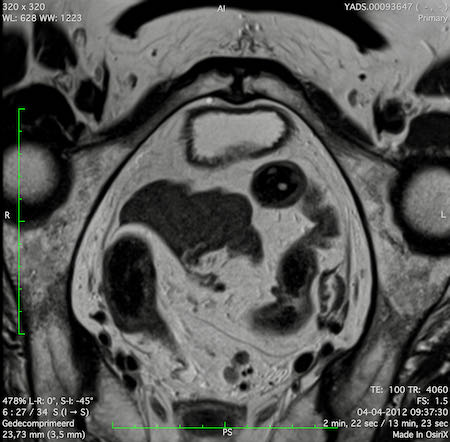

Hình ảnh

Các hình ảnh được cung cấp cho thấy ung thư biểu mô tế bào nhẫn với tình trạng dày lan tỏa thành trực tràng, hình ảnh bia bắn điển hình, và sự xâm lấn mỡ mạc treo trực tràng.